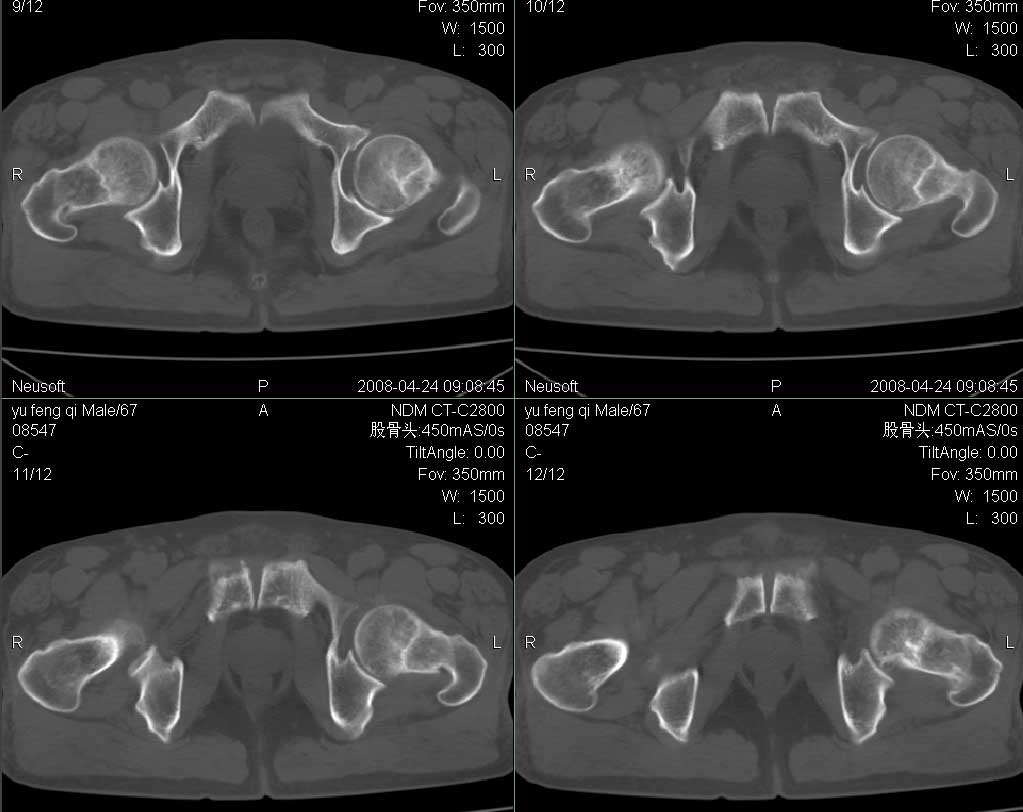

标题: CT13069:双髋关节 [打印本页]

标题: CT13069:双髋关节

男67岁,左髋疼痛破行2月。

左侧髋关节积液,无菌坏死待排,建议mri检查

建议行mri检查排除左侧股骨头无菌性坏死。

左髋关节积液,建议mr检查。

支持左侧髋关节少量积液.

支持双款关节轻度退变,左髋关节少许积液

ct平扫未见明显异常,建议行mri检查排除左侧股骨头无菌性坏死早期改变。

其它退行性改变。